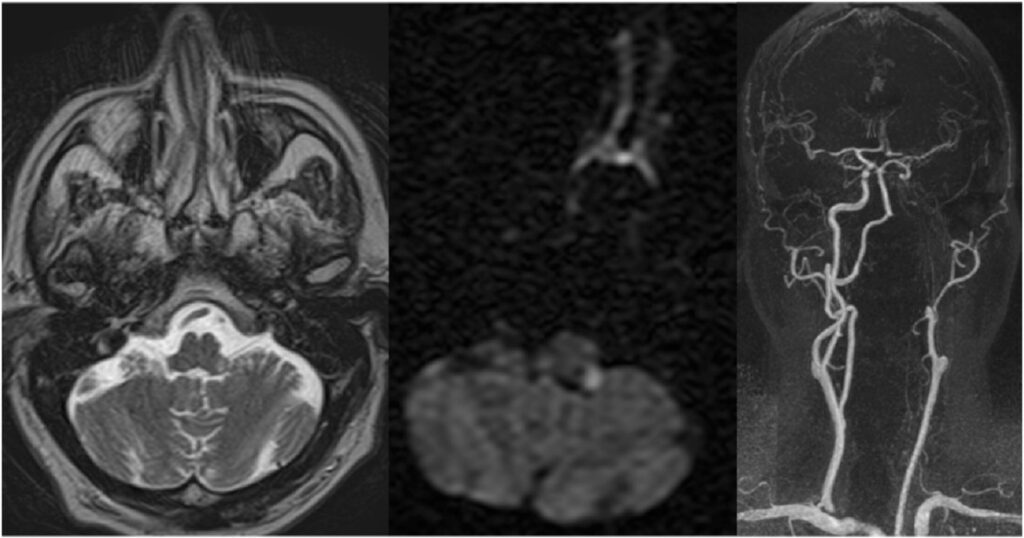

El presente caso ilustra un infarto isquémico del mesencéfalo medial, con una distribución paramediana bilateral y predominio a nivel del tegmento, acompañado de extensión caudal limitada hacia la unión pontomesencefálica. Este patrón topográfico, identificado mediante la combinación de secuencias de difusión y mapas ADC, es característico de la afectación de las ramas perforantes paramedianas del segmento distal de la arteria basilar y/o del segmento proximal de la arteria cerebral posterior, responsables de la irrigación del mesencéfalo medial, y ha sido descrito en infartos mesencefálicos mediales bilaterales dependientes de estas ramas perforantes.(5, 16)

En términos topográficos, la bilateralidad y simetría de la lesión constituyen un elemento clave para su correcta interpretación. A diferencia de los síndromes mesencefálicos alternos clásicos, como los síndromes de Weber o Benedikt, en los que el compromiso es típicamente unilateral y se extiende hacia los pedúnculos cerebrales, en este caso la lesión se encuentra confinada al tegmento medial, sin afectación significativa de las estructuras laterales, patrón previamente reportado en series imagenológicas de infartos mesencefálicos mediales.(5, 16) Este hallazgo permite descartar un patrón peduncular y refuerza el diagnóstico de un infarto mesencefálico medial.

La extensión rostro-caudal observada, con compromiso adicional del puente rostral, no debe interpretarse como la coexistencia de lesiones independientes, sino como la expresión de un territorio vascular continuo, fenómeno descrito en infartos dependientes de perforantes paramedianas largas.(17, 18) En este contexto, el análisis del eje rostro-caudal resulta tan relevante como la evaluación dorsoventral, en especial en lesiones localizadas en zonas de transición anatómica.

En este caso, la lesión se localiza predominantemente a nivel del mesencéfalo medial, con una distribución paramediana bilateral y extensión caudal limitada hacia la unión pontomesencefálica. Este patrón topográfico permite integrar los hallazgos imagenológicos dentro de un infarto mesencefálico medial y diferenciarlos de otros síndromes mesencefálicos clásicos con compromiso lateral o peduncular.(5)